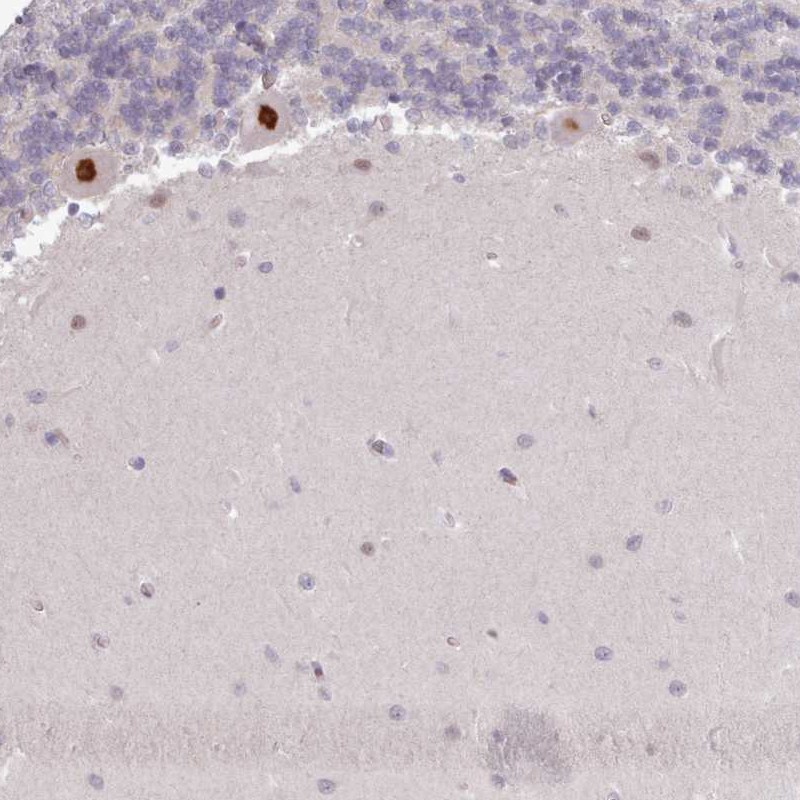

Immunohistochemical staining of human cerebellum shows strong nuclear positivity in Purkinje cells.